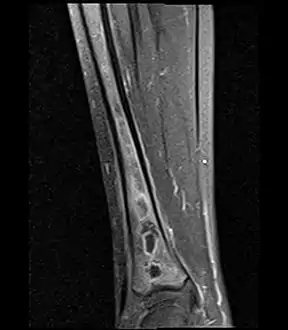

a,b) MRI showing the Brodie's abscess in the left proximal femur

A Brodie abscess is a subacute osteomyelitis, which may persist for years before progressing to a chronic, frank osteomyelitis. Classically, this may present after progression to a draining abscess extending from the tibia out through the skin. Occasionally acute osteomyelitis may be contained to a localized area and walled off by fibrous and granulation tissue.

Usually occurs at the metaphysis of long bones. Distal tibia, proximal tibia, distal femur, proximal or distal fibula, and distal radius.

Oval, elliptical, or serpentine radiolucency usually greater than 1 cm surrounded by a heavily reactive sclerosis, granulation tissue, and a nidus often less than 1 cm. The margins often appear scalloped on radiograph. Brodie's abscess is best visualized using computed tomography (CT) scan. Associated atrophy of soft tissue near the site of infection and shortening of the affected bone. Osteoblastoma may be a classic sign for Brodie's abscess.